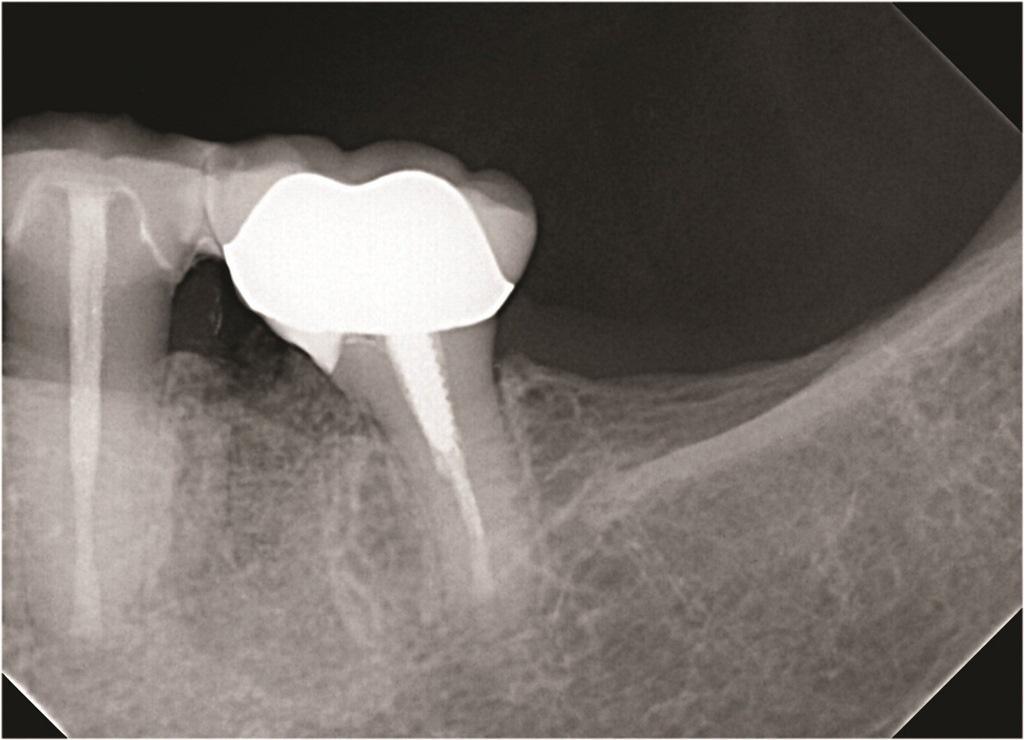

Фото 2: Зуб 4.6 с ранее проведенным апикальным хирургическим вмешательством, показывающий потерю кости вокруг переломанного мезиального корня.